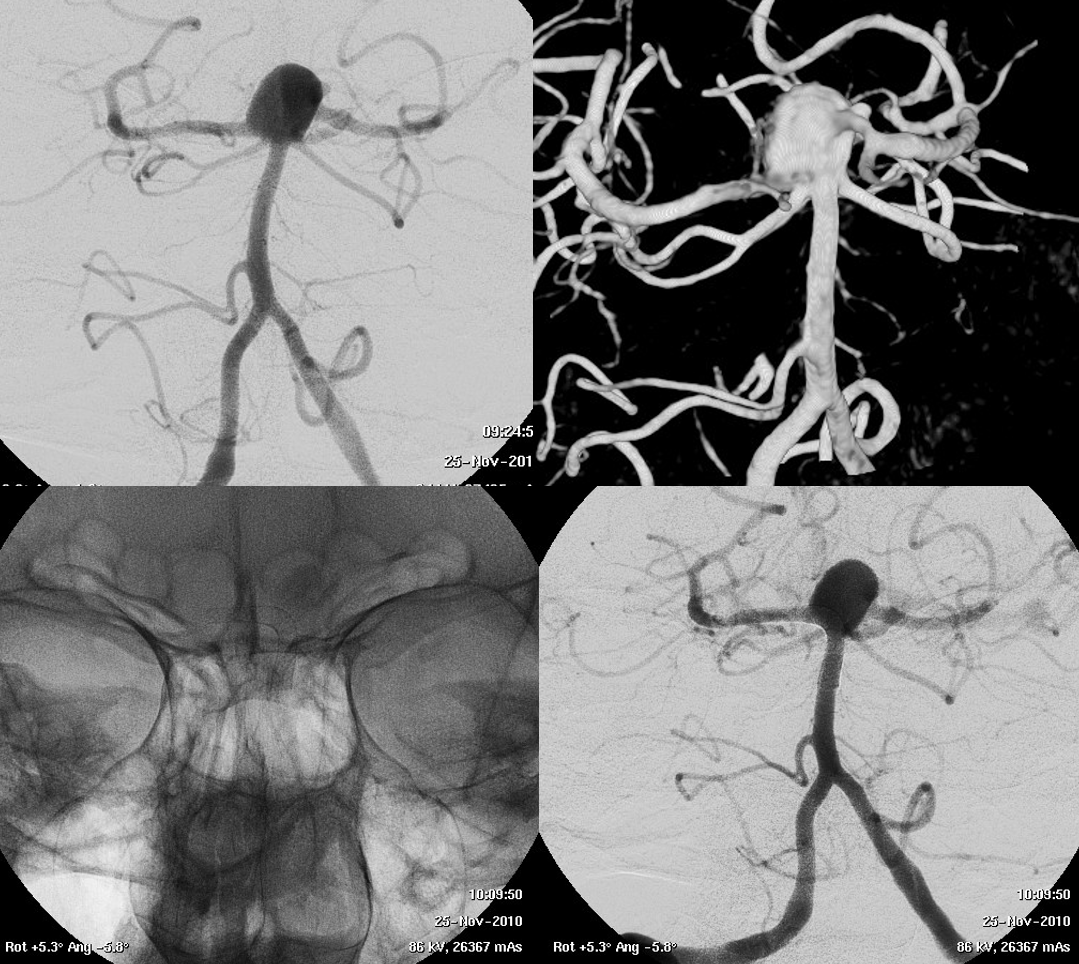

Very Important Case of Aggressive Basilar Bifurcation Aneurysm

Unruptured basilar tip aneurysm treated in 2010 with PED between right P1 and basilar.

Make sure you don’t judge — we know much more about how these behave now than in 2010 — and many people today still coil these with laser-cut stents and mess up options for the guaranteed recurrence

The aneurysm was kept open by the left (contralateral) PCom — again, we know this much better now than in 2010. And its very important.

13 year later. The aneurysm was mostly thrombosed and was growing, becoming symptomatic. The good old analog Philips workhorse is gone… Welcome to the digital world or Azurion

With manual compression of the left carotid — look how important manual compression or Balloon Test Occlusion can be

Left ICA — the preferential supply to bilateral SCAs is clearly seen

3D reconstructions of the left ICA (3D 5 seconds acquisition, 22 cm FOV, manual injection of pure contrast – 300 mg/ml – with a 20 ml syringe, no secondary reconstructions). Both the SCAs are injected by the PCom and the right SCA origin is shaped by the PED in right P1. Now in left P2 there is a fusiform dilatation, not present before